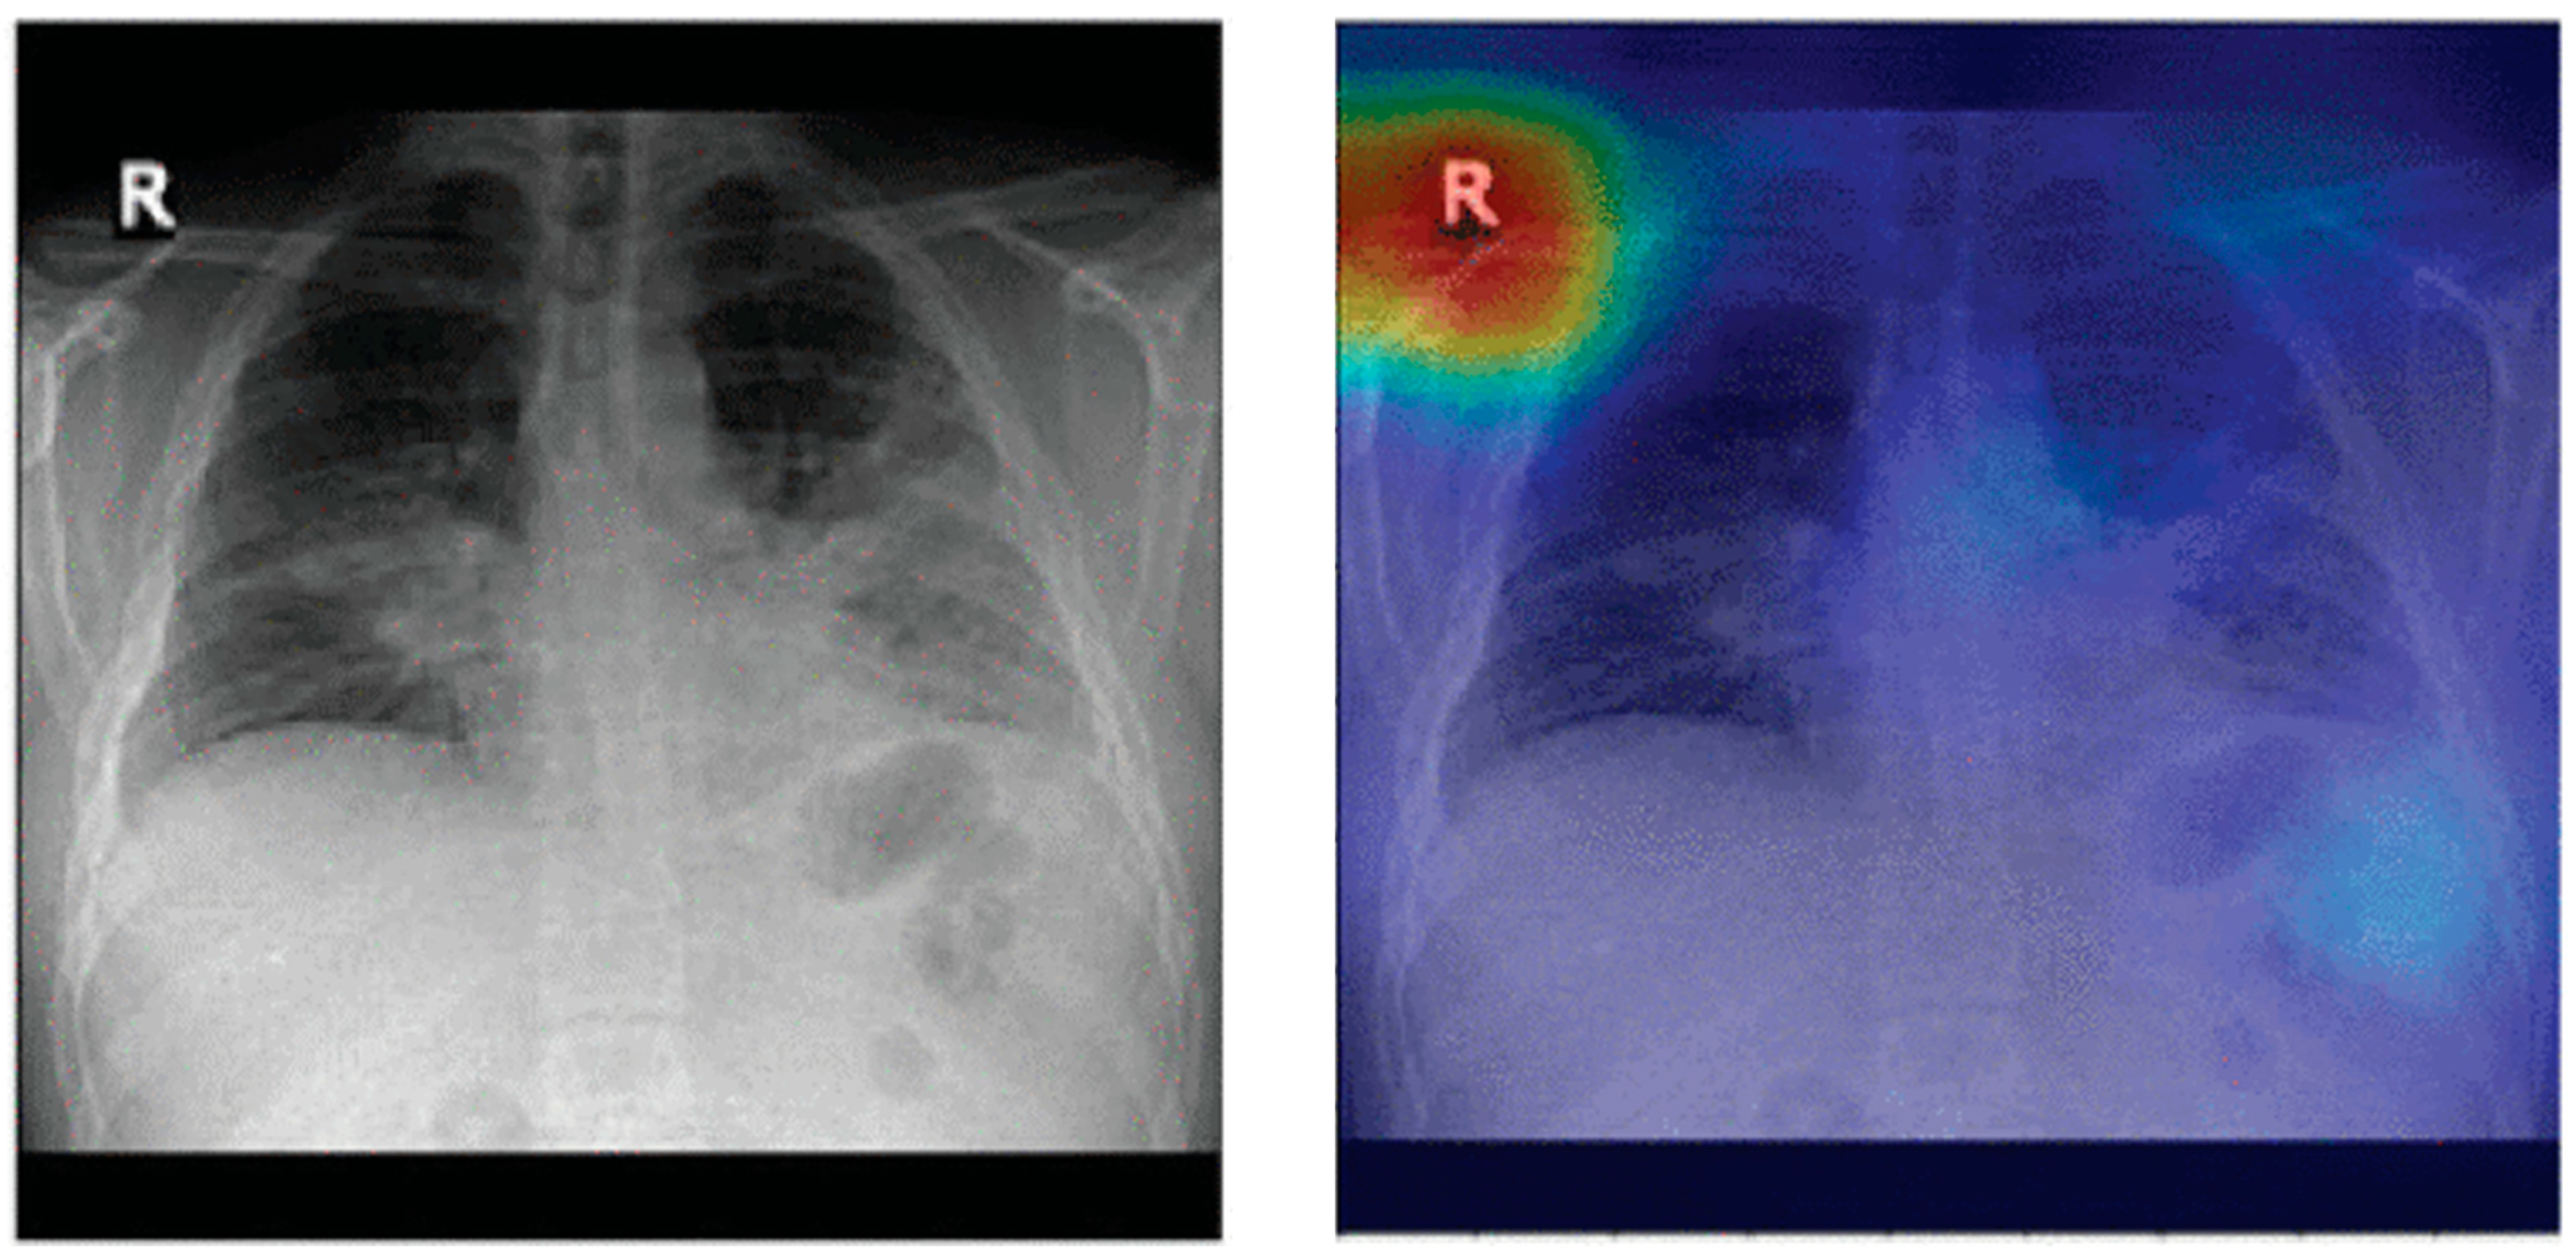

- Selvaraju, R.R.; Cogswell, M.; Das, A.; Vedantam, R.; Parikh, D.; Batra, D. Grad-CAM: Visual Explanations from Deep Networks via Gradient-Based Localization. Int. J. Comput. Vis. 2020, 128, 336–359. [Google Scholar] [CrossRef]